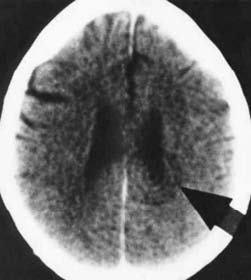

Hamer Focus (HH) in ring form configuration at the beginning of the healing phase

The larger the HH, the larger is the tumor, the necrosis or the cell alteration on the corresponding organ. The more intensive the conflict, the faster does the tumor grow or the larger is the necrosis, the osteolysis or the cell alteration with those cancers that do not display cell augmentation.

During this phase there is temporary swelling of the brain which can cause problems, e.g. if the conflict has lasted too long, or when the brain edema is located in an unfavorable location, or when the HH shows an intra- and perifocal edema. The edema on the organ and on the correlating HH in the brain grows particularly large with a simultaneous kidney collecting tubule-water retention conflict, which we call “The Syndrome”. At this point the HH requires more room, consequently indenting surrounding brain tissue or pushing it out of the way.

In the brain both phases (conflict active phase and resolution phase) have the HH at the same location. They are, however, in different conditions: During the conflict active phase the HH appears as a sharp ring configuration while during the resolution or healing phase the HH appears as swollen, edematous and dark. At the end of the healing phase so-called glia, harmless brain connective tissue is stored at the site participating in repairing the HH.

The white dense glia HHs, which can be easily made visible in a computer tomogram using iodine contrast substance, indicate a repair process on the HH in the brain and are not at all a reason to panic.

After the healing phase the HH shows as a harmless scar – the end result of a successfully completed healing process. The glia-rings are unfortunately misinterpreted as “brain tumors”, as glioma, astrocytoma, oligodendroglioma, glioblastoma etc. and are cut right out to the disadvantage of the patient. Since brain cells can no longer divide after birth brain tumors do not really exist!

Right arrow: HH in right temporal lobe Condition after heart attack (territorial conflict)

Left arrow: testicular carcinoma (profound loss conflict) for right testicle (already in healing phase)

In this example, the patient, a farmer, had suffered a DHS six months earlier, when his only son had a serious motorcycle accident. The son spent a long period of time in intensive care, and the patient thought that his son would remain physically disabled. But his son fully recovered. Four weeks after the son returned to the farm, his father suffered a heart attack with dizziness, headaches and balance disturbances. He suffered the heart attack after he had resolved the conflict.